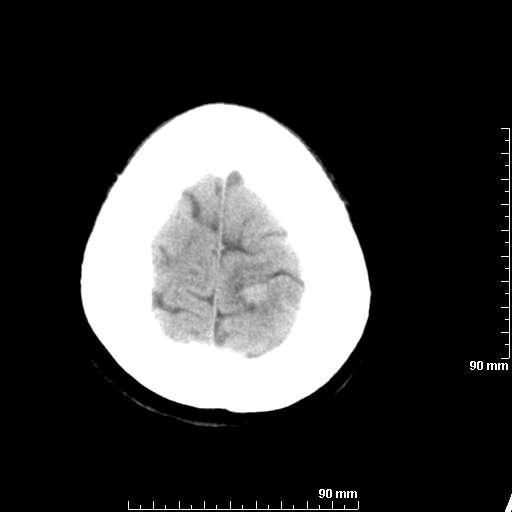

我院西门子单排CT由于一零件受损而产生的伪影.

哈哈,都不是。是虑线器fiter裂损。大家没想到吧。

哦,跟脑出血有点像哦

形状不规则,边缘模糊。比较特殊的一种伪影哈!

这种伪影很常见!伪影应该是在视野的中心的。

西门子的虑线器fiter裂损这才是很难见的问题,GE的最常见

虑线器老化,中间崩裂一块掉了